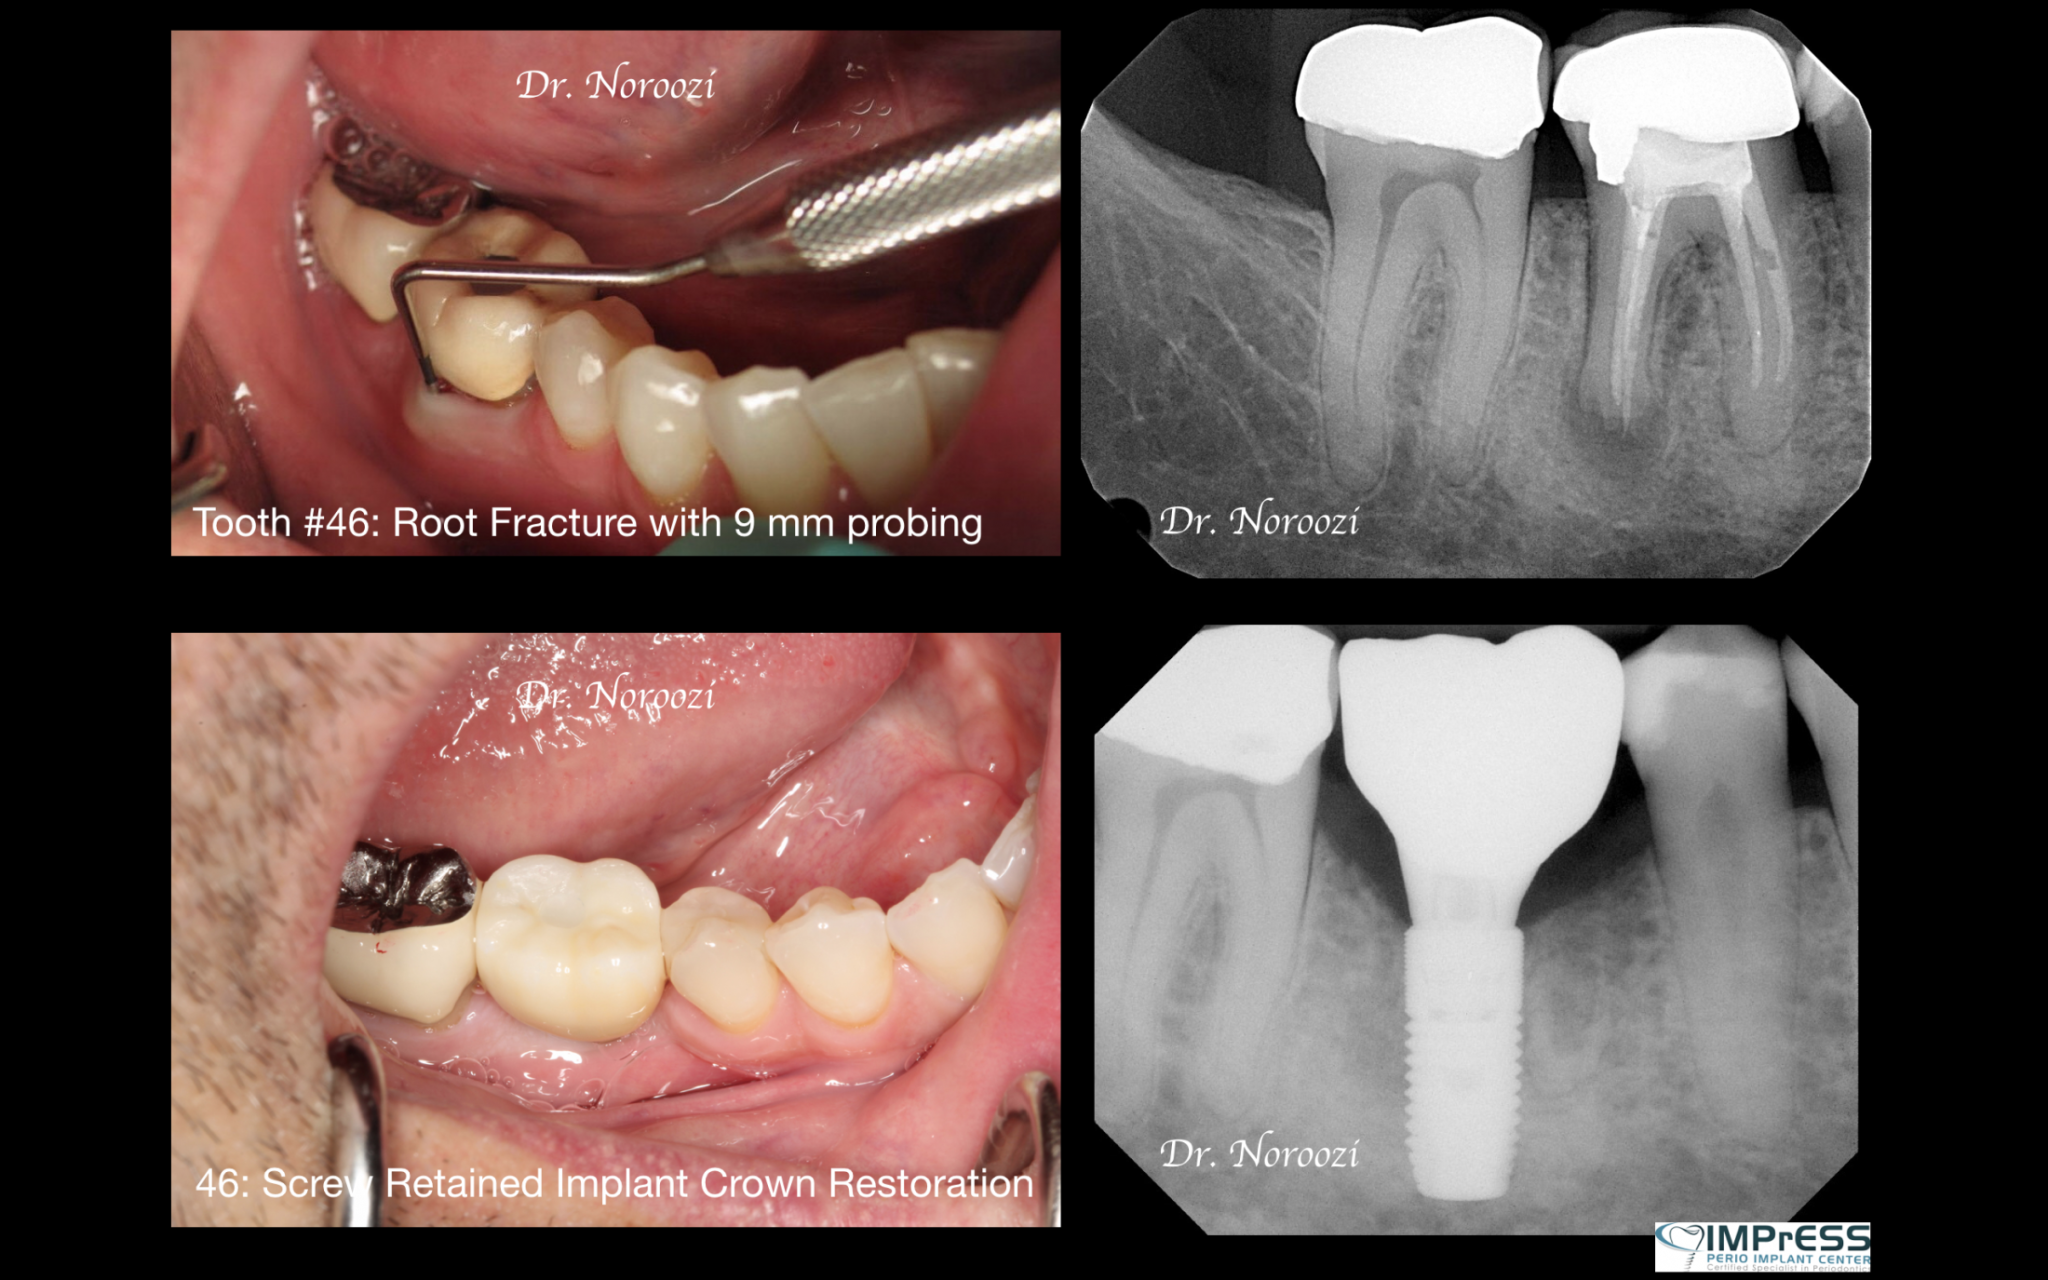

Before & Afters of Dental Implant Patients

Complete Dental Implant Cases Gallery

General Disclaimer: The results in the photographs are examples only and do not imply any certainty of the result of a procedure, and all outcomes are subject to the circumstances of the individual patient.